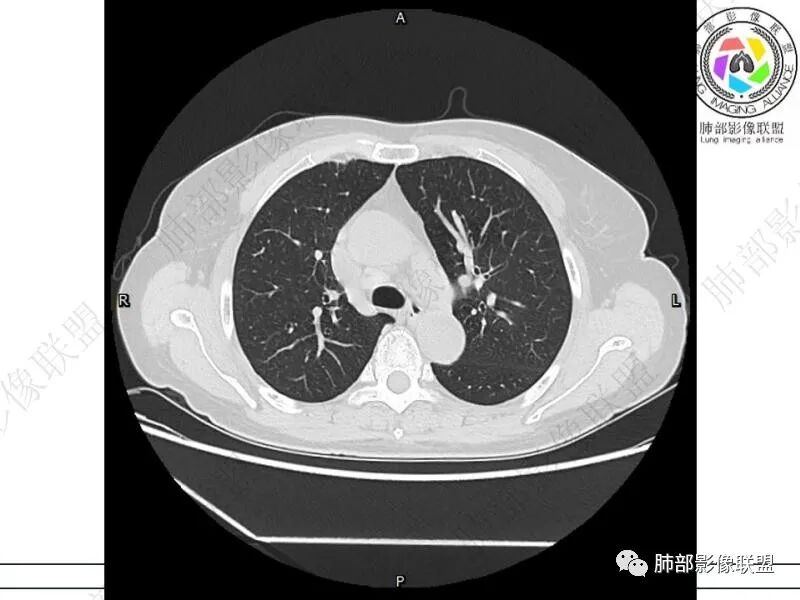

摘星空竹子:两肺胸膜下多发实性结节、磨玻璃影及实变影,短期复查病变有所进展,考虑感染性病变,隐球菌可能,患者有右半结肠癌手术史,转移不能除外。

简单:双肺及胸膜下多发小结节,双下肺胸膜下宽基底团块影,短期内病灶进展考虑炎性病变,隐球?患者ca术后,双肺小结节随诊除外转移

丽:双肺下叶胸膜下多发片状高密度影,边缘模糊不清,内可见支气管穿行,病变长轴平行于胸膜,考虑感染性病变,隐球菌

媛:肠癌术后,免疫力低下。两肺胸膜下结节及实变影,实变影长轴平行于胸膜,密度均匀,边界偏清,周围有晕征,短期复查进展,虽隐球菌荚膜抗原检测阴性,还是考虑隐球菌,鉴别OP

谢加平:结肠癌术后史,两肺胸膜下多发结节及斑块实变病灶,实边边界平直征(亚急性和慢性病变过程),双肺下叶后基底段胸膜下为甚,与胸膜平行特点,见支气管充气征,边缘模糊的GG0,首诊2022年11月18日肺部CT,与治疗11月28日对比,病灶未吸收,双肺下叶胸膜下病灶有侧向融合特点,综合分析符合炎性肉芽肿,隐球菌感染。

老年女性,结肠癌术后。两下肺胸膜下为主片状实变,右下肺短期复查融合且病灶长轴平行于胸膜,实变内可见支气管充气征,边缘磨玻璃晕,另两肺内胸膜下散在数枚小结节状、楔形实性灶。考虑感染性病变,隐球菌可能,鉴别肺转移。

2.影像特征:双肺胸膜下多发实性结节、磨玻璃影及实变影,胸膜下优势分布、晕征、胸膜下脂肪间隙存在,部分病灶边界平直征,有侧向融合趋势。